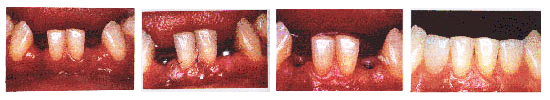

人工种植牙是现代治疗牙齿缺失的最先进镶牙技术(被称为人类的第三副牙齿)。

就是在缺牙区植入钛金属的人工牙根,待人工牙根与周围骨组织形成“骨结合”后,就可以镶上一颗理想牙齿。其形态、功能,犹如天然牙齿一样。自然美观。

不用磨损健康牙齿,哪儿缺种哪儿。

稳固、咀嚼功能得到最佳的恢复。

感觉舒适,自然美观,形态逼真。